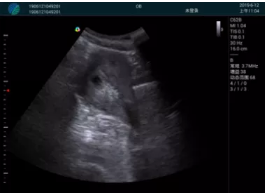

病例二:

甲狀腺囊性結(jié)節(jié),囊壁鈣化,透聲好

甲狀腺囊性占位